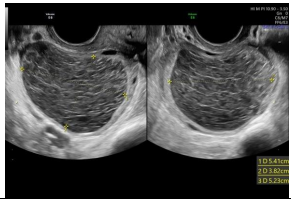

Observe a imagem a seguir.

Sobre as malformações uterinas, os critérios diagnósticos revelados na imagem se correlacionam a qual diagnóstico de malformação mülleriana?